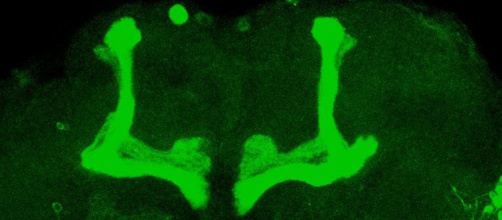

Un seul gène peut dérégler le sommeil